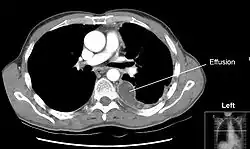

В области корней лёгких париетальная плевра, прилегающая к средостению (медиастинальная плевра), переходит в висцеральную плевру. В свою очередь, соединительная ткань, формирующая висцеральную плевру, проникает в ткань лёгких, образуя интерстициальный лёгочный каркас, а также выстилает поверхности долей лёгких в междолевых щелях. Плевра, выстилающая боковые поверхности грудной полости (рёберная плевра) и медиастинальная плевра внизу переходят на поверхность диафрагмы, образуя диафрагмальную плевру. Места перехода плевры с одной поверхности лёгкого на другую называются плевральными синусами; они не заполняются лёгкими даже при глубоком вдохе. Различают рёберно-диафрагмальные, рёберно-медиастинальные и диафрагмально-медиастинальные синусы, ориентированные в различных плоскостях. В плевральных синусах, особенно самых низкорасположенных задних рёберно-диафрагмальных, в первую очередь накапливается жидкость при развитии гидроторакса (см. рисунок). Иннервируется плевра блуждающими, межрёберными и диафрагмальными нервами. В париетальной плевре располагаются болевые чувствительные рецепторы.